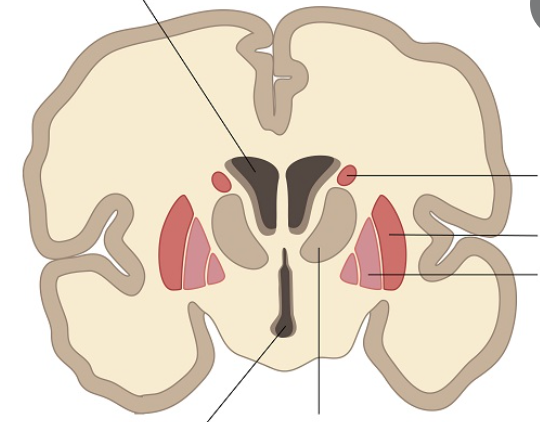

Label the ventricles of the brain & the parts of the basal glanglia

Fill in the blanks